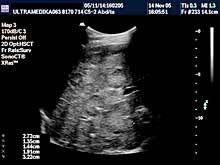

Pregledi abdomena

Standardni pregled podrazumeva pregled svih organa stomaka:

jetra, žučna kesa, žučni putevi, pankreas, slezina, bubrezi, limfne

žlezde,

cevasti organi, veliki krvni sudovi,

pleuralni prostori, prednji trbušni zid. |